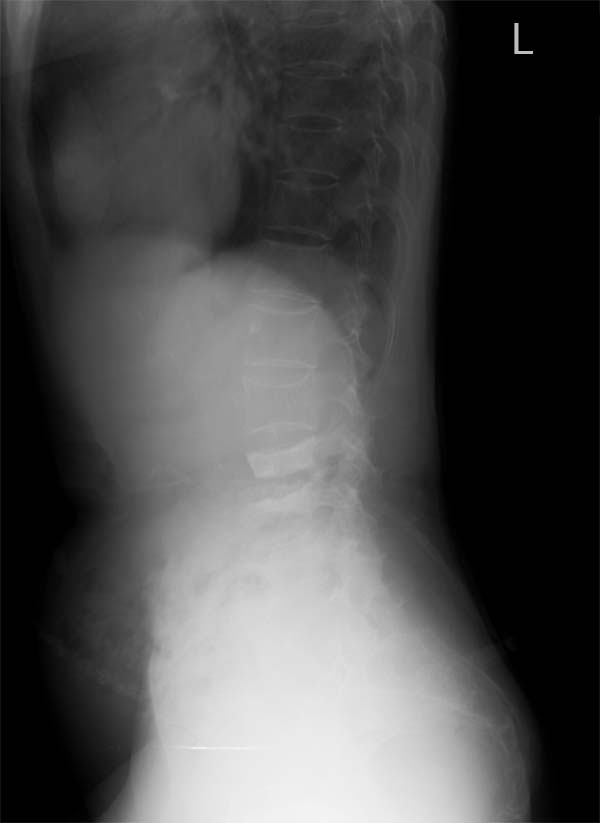

以下是引用hhcckk在2007-7-27 17:40:00的发言:[br]l3、4椎体压缩变扁,椎间隙增宽,考虑转移瘤可能性大[br]1、结核一般多有椎间隙的狭窄(当然中央型的可无椎间隙的狭窄,但毕竟少见,而且到后期也会累及椎间隙),椎旁的寒性脓肿,好发年轻人,好发于胸椎,临床有结核中毒症状,种种征象都不太支持[br]2、骨软骨炎、嗜酸性肉牙肿可以使椎体压缩变扁,椎间隙无狭窄,甚至可以增宽,但这两种病多好发于年轻人,年纪大的还是首先排除转移性肿瘤再考虑其它的疾病吧

以下是引用听蝉观竹在2007-7-28 21:05:00的发言:[br]这个病例有几个影像特点:1、病变为2个腰椎椎体,2、椎体有明显和压缩,密度明显增高,第4腰椎椎体见皮质破坏;2、椎间隙无狭窄,而且变宽。[br]分析:[br]1、上述影像改变不符合脊椎结核,因为脊椎结核主要病变是先累及椎体边缘软骨和椎间盘,所以象x线表现主要的改变是-------椎间隙变窄和椎体边缘的破坏。而本病例恰恰相反------椎间隙无狭窄,而且变宽。[br][br]2、这个病例符合脊椎转移性骨肿瘤的表现-----多个椎体的的破坏和病理压缩性骨折、椎间隙无狭窄,而且变宽。[br][br]3、女性,60岁,又普遍存在骨质疏松,应该注意与骨质疏松的压缩骨折向鉴别。对这个病例我分析-----(1)[br]病变是在腰3、4椎体,而不是胸12、腰1椎体,不符合压缩骨折的受力特点;(2)第4腰椎椎体见明确骨皮质破坏。所以我考虑转移性骨肿瘤可能性要远大于骨质疏松的引起的压缩骨折。[br][br]4、老年女性,脊椎转移性骨肿瘤,寻找原发肿瘤首先应该查乳腺、甲状腺、生殖腺。[br]